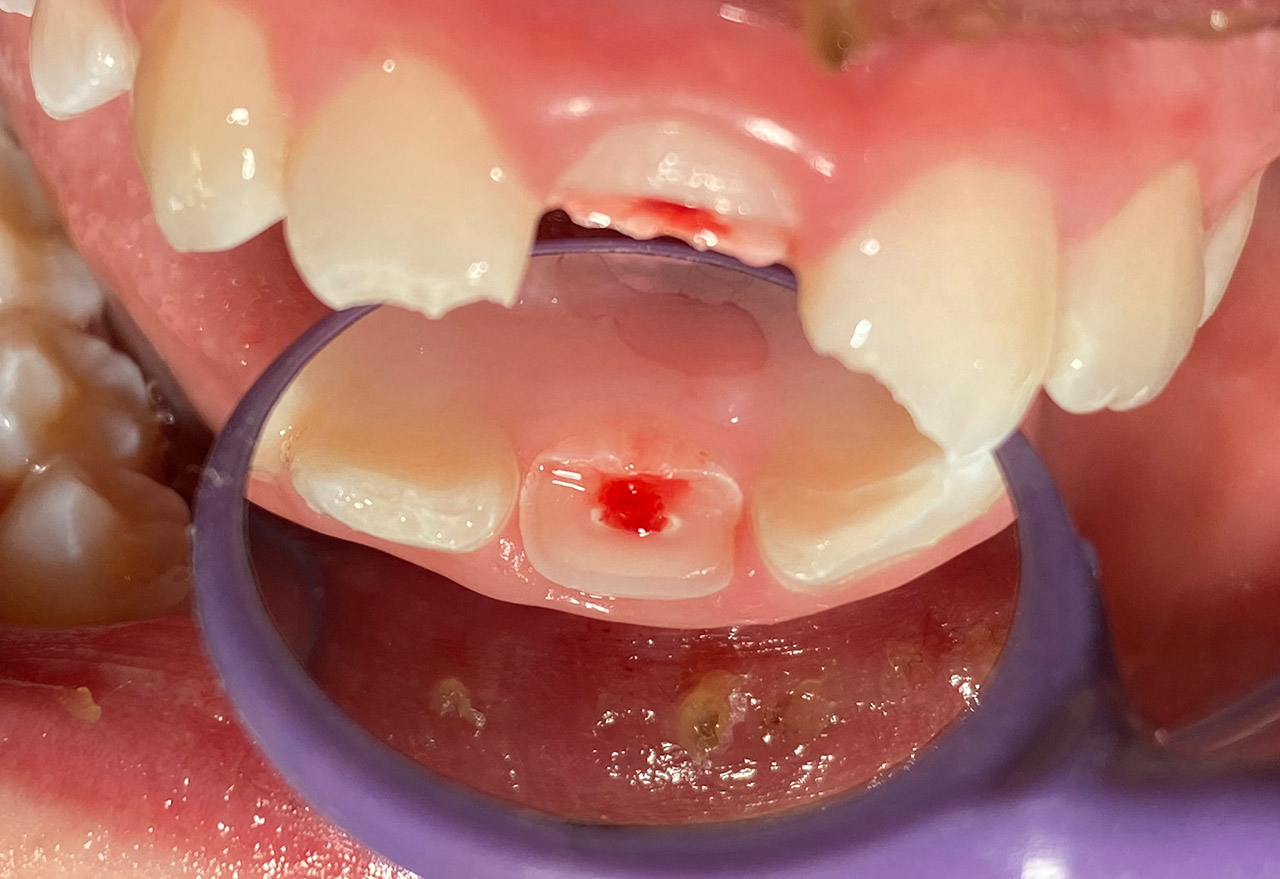

Traumatologie und Endodontie:

Nach Unfall/Sturz mittlerer Schneidezahn auf Gingivaniveau abgebrochen, Pulpa weit eröffnet, beide Nachbarzähne ebenfalls frakturiert.

Erstversorgung: Pulpektomie der Kronenpulpa, MTA, provisorischer Verschluß mit rosa Glasionomerfüllung.

Wiederaufbau der Nachbarzähne mit mitgebrachten (plus 1 Stein) Zahnstücken mit Kunststoff ergänzt und adhäsiv verklebt.

2. Schritt nach Aushärtung von MTA: Entfernung der Kronenpulpa im Bruchstück zur Vermeidung von Verfärbung, Füllung mit Kunststoff.

Adhäsives zementieren des abgebrochenen Zahnstücks.